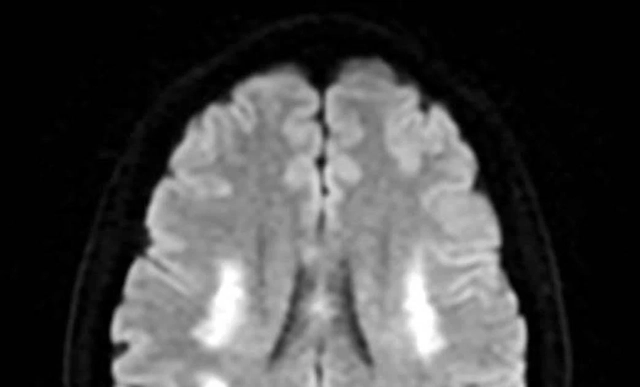

Nữ bệnh nhân đột quỵ bác sĩ chỉ ra nguyên nhân bất ngờ- Ảnh 2.

Hình ảnh kiểm tra mạch máu não của người bệnh không ghi nhận tình trạng tắc hoặc hẹp các mạch máu lớn (ảnh: BSCC)